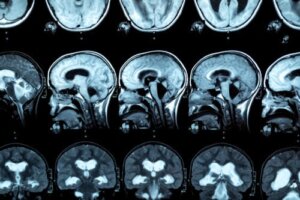

It is characterized by demyelination, as well as eventual necrosis, of the corpus callosum. What does this mean? The corpus callosum is a structure located in the brain that connects the two hemispheres, helping both to work in a coordinated manner.

Tumefaction of the corpus callosum can also be appreciated if a cerebral image is made. In some cases, signs of interhemispheric disconnection syndrome are present.

For the diagnosis of this pathology, an MRI is performed, so that lesions in the corpus callosum are observed. In this regard, research indicates that people with alcohol use disorder show a reduction in the anterior, middle, and posterior thickness of the corpus callosum, as well as variations in the size of the frontal lobe and cortical sulci.